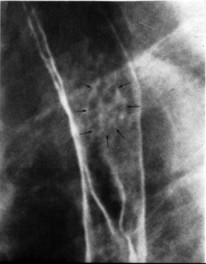

Forme

infiltrant avec expension segmentaire de la lumiere

. Aspect microspicule de la muueux |